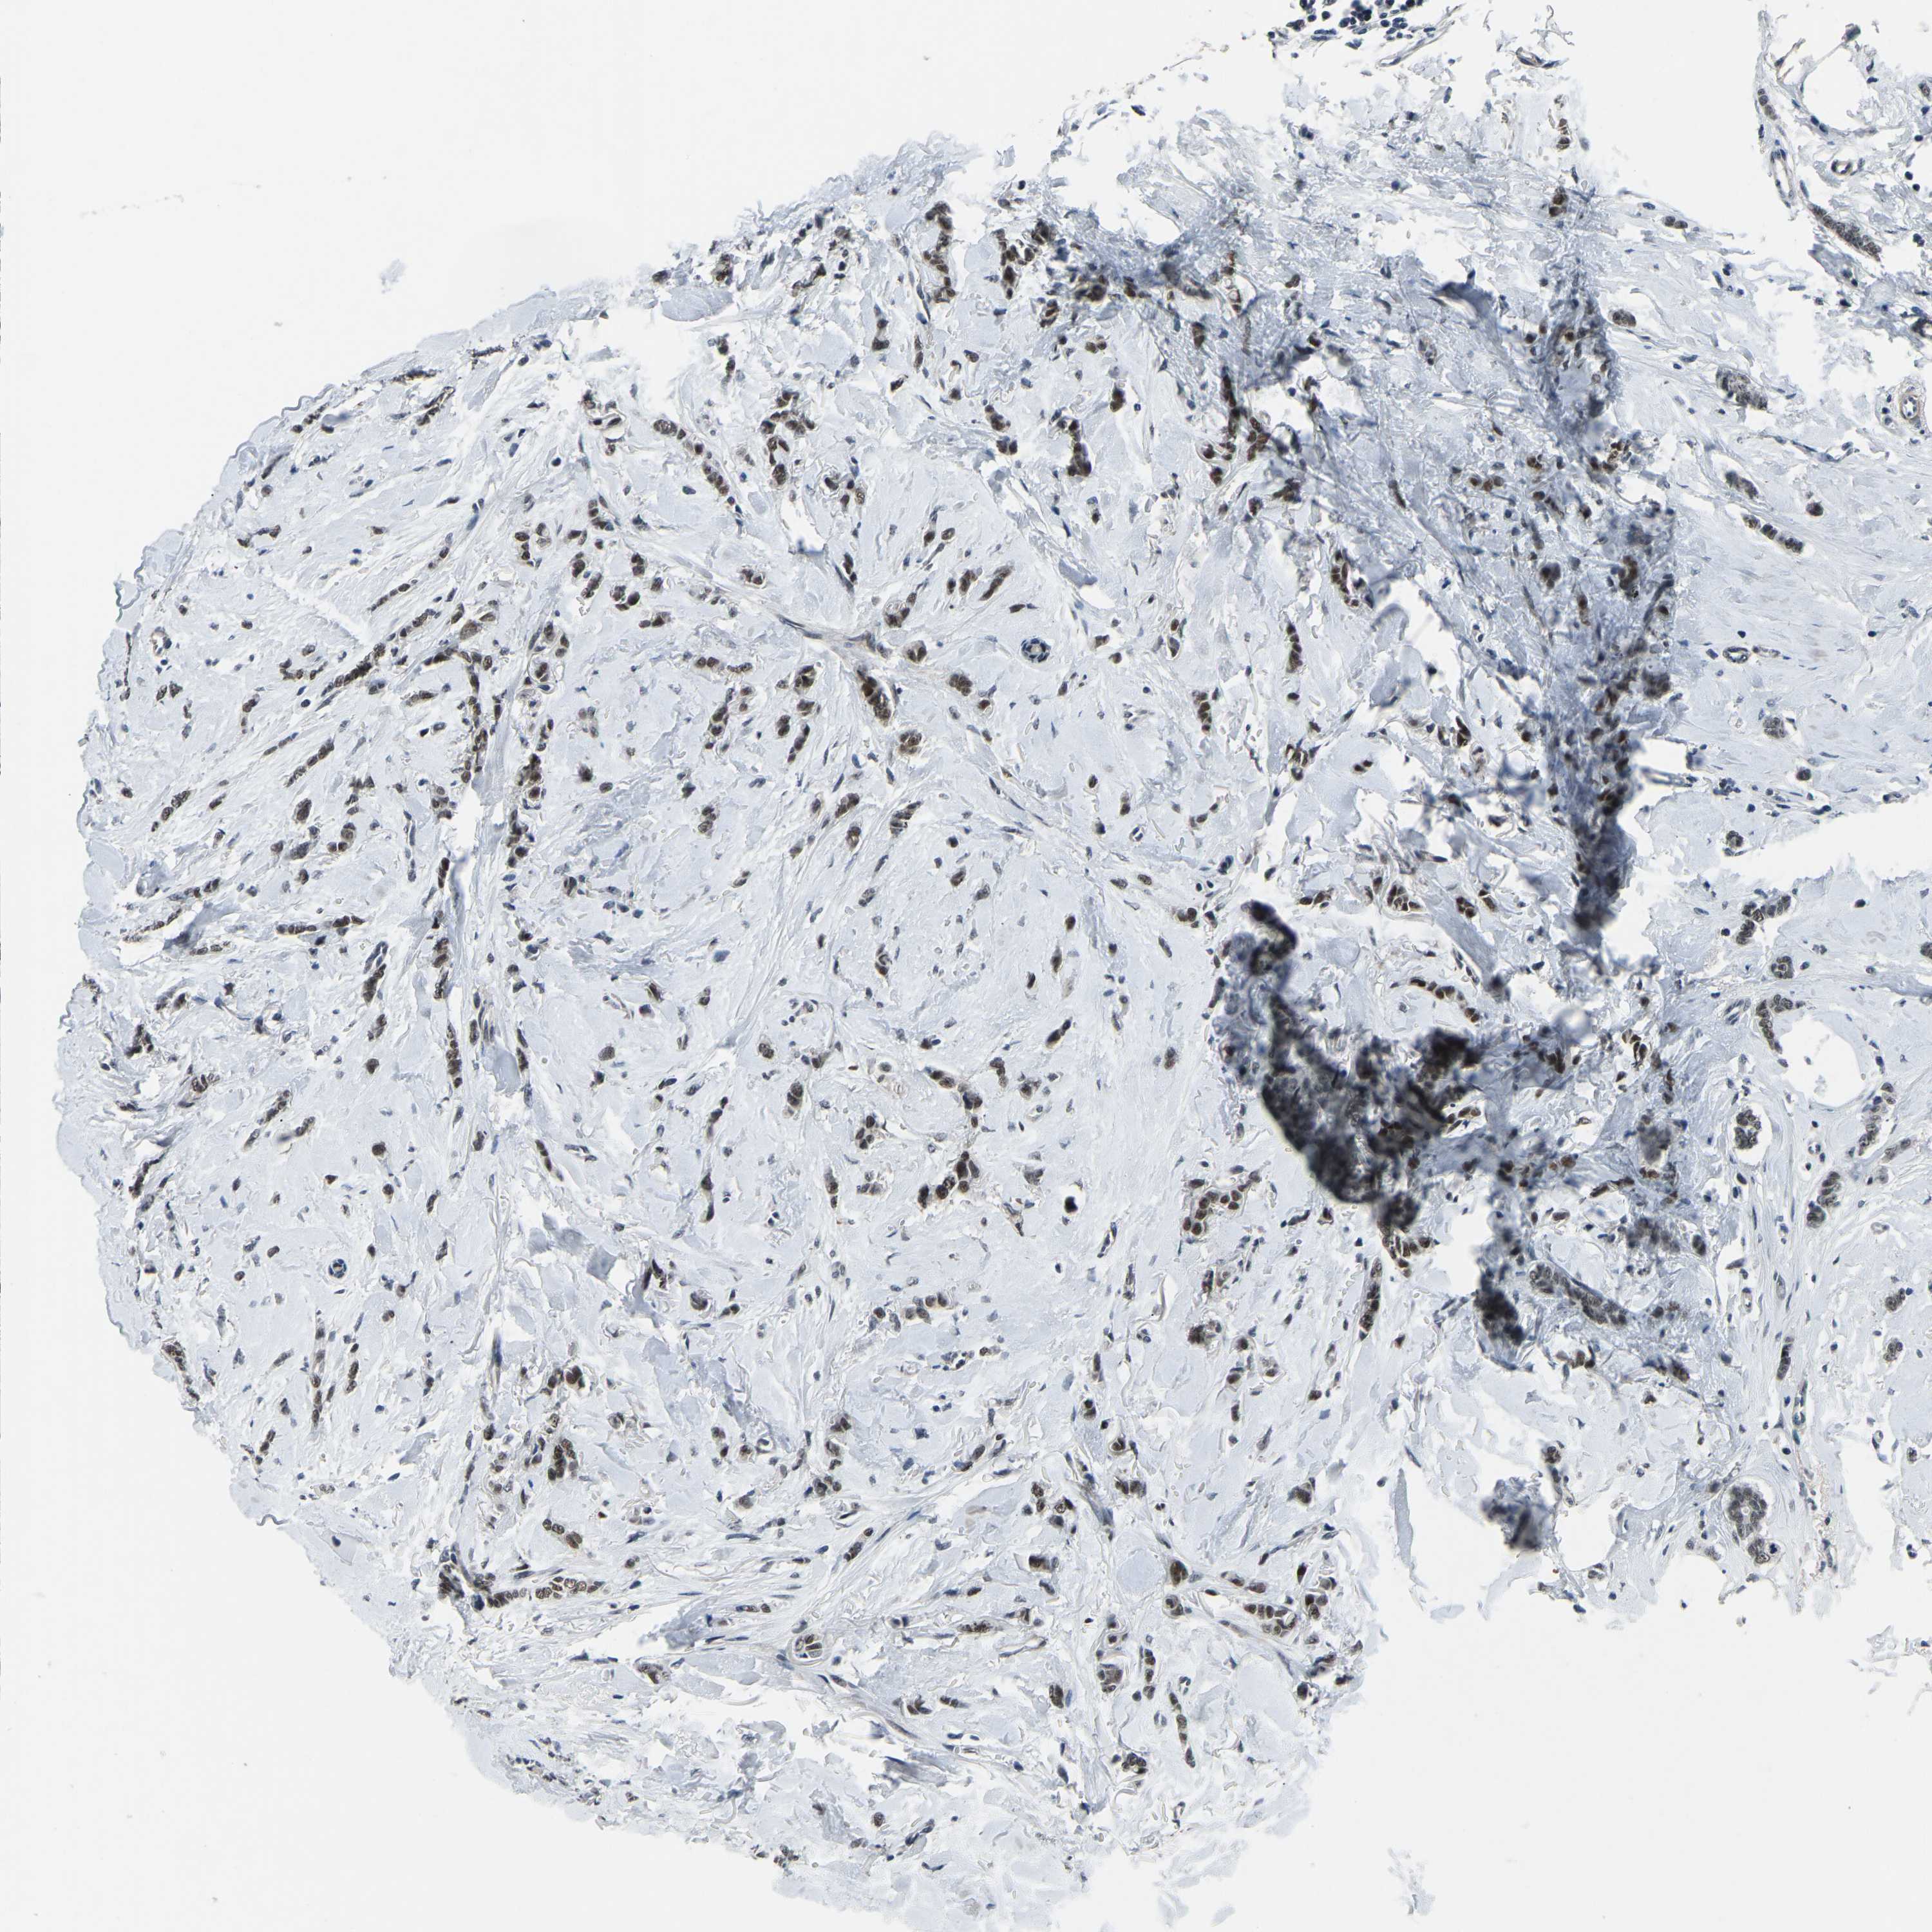

BRCA TCGA BRCA VALIDATION PROTEIN EXPRESSION